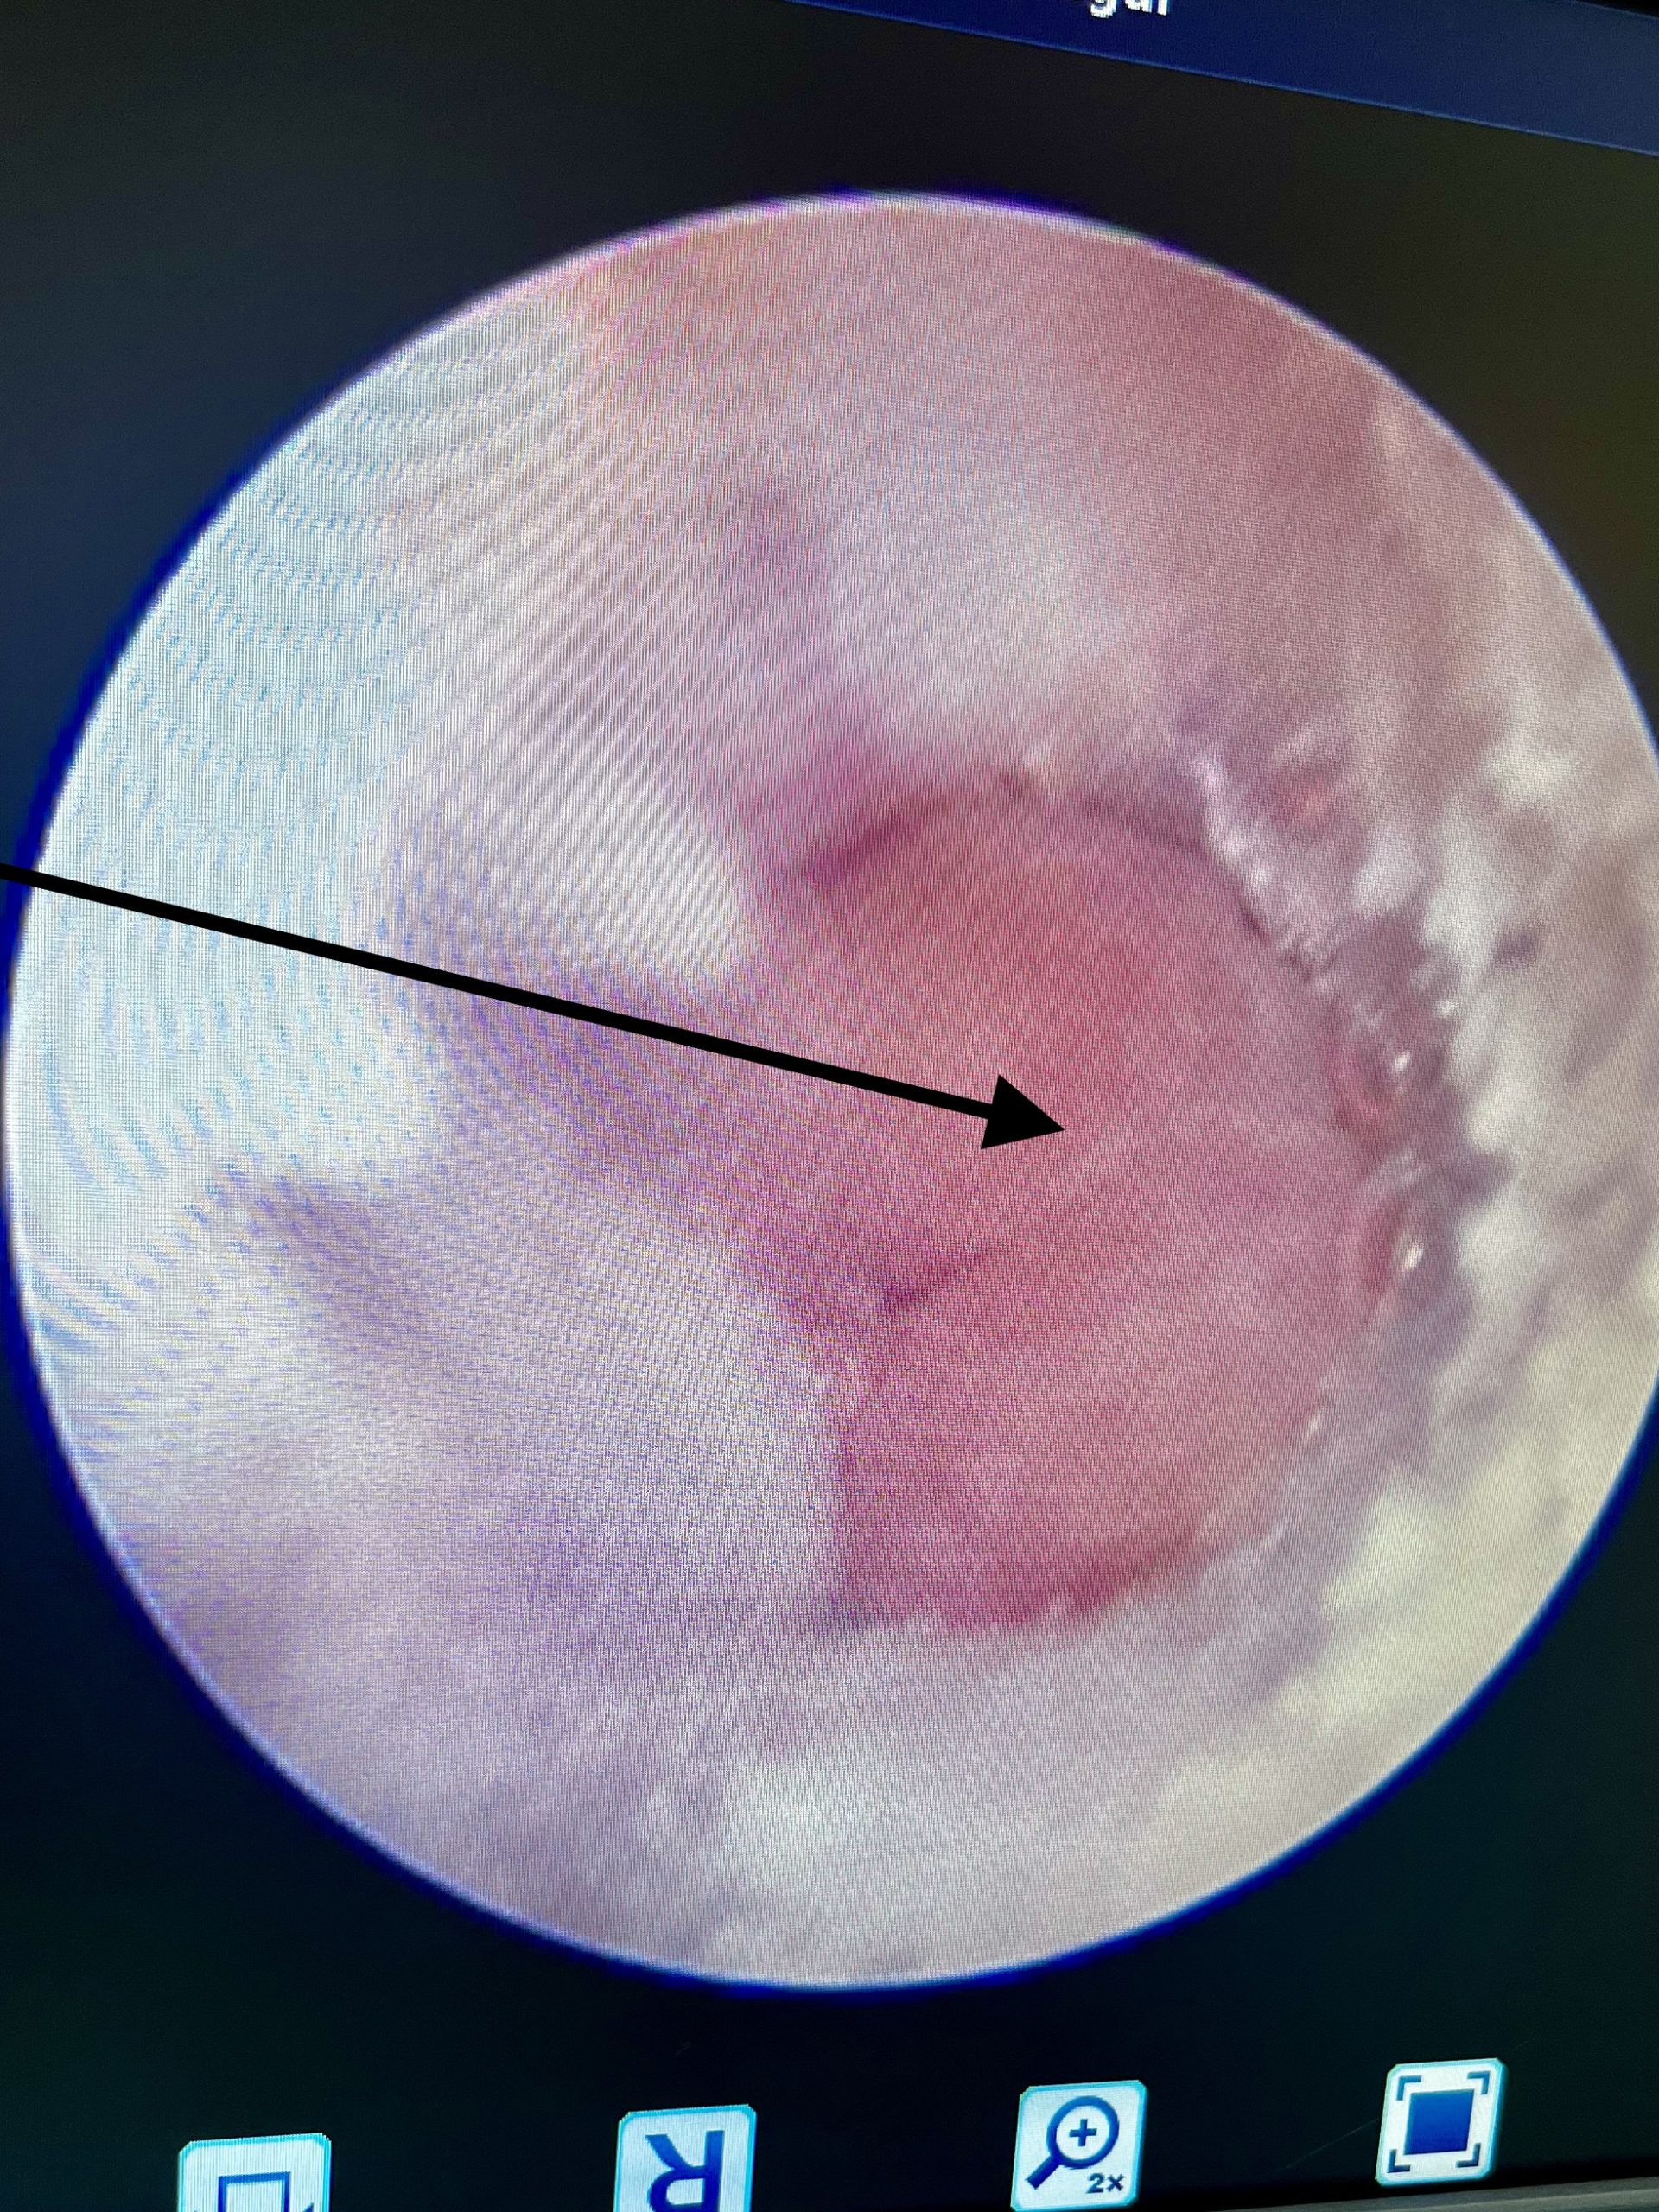

Öronspolning med videoendoskop är en specialutrustning där man med en videokamera kan se hela hörselgången, trumhinnan och in i mellanörat. Under spolningen ser man allt man gör på en videoskärm och kan effektivt spola rent hörselgången ned till trumhinnan. Det ger även möjlighet att punktera trumhinnan för att kunna provta och spola mellanörat om det behövs. Man kan även lättare operera ut tumörer eller ta biopsier på vävnadsförändringar via denna teknik.

Öronspolning hos oss görs med så kallad videootoskopering, vilket är ett endoskop med videokamera som ansluten till en spolmaskin. Med denna utrustning ser man precis vad man gör och kan exempelvis punktera trumhinna och spola ur mellanörat. Djuret sövs och tubas i narkos för att inte få sekret och spolvätska i lungorna.